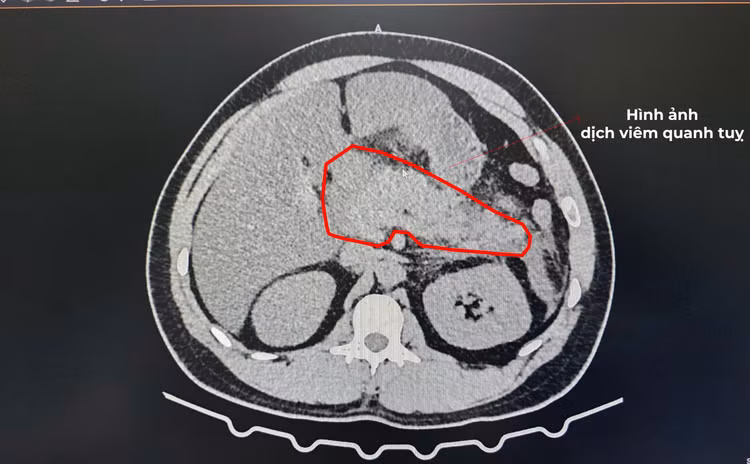

Hình ảnh chụp cắt lớp vi tính (CLVT) cùng các xét nghiệm cận lâm sàng đã xác định rõ tình trạng viêm tụy cấp nặng. Bệnh nhân được chẩn đoán viêm tụy cấp do tăng triglycerid máu và nhanh chóng được xử trí theo phác đồ chuyên môn, theo dõi sát toàn trạng, nhịn ăn giai đoạn đầu, nuôi dưỡng tĩnh mạch, đặt sonde dạ dày, bù dịch tích cực, sử dụng kháng sinh phối hợp liều cao, giảm đau, giảm tiết dịch vị dạ dày và kiểm soát chặt chẽ mỡ máu. Khi tình trạng lâm sàng cải thiện, bệnh nhân được chuyển dần sang chế độ ăn phù hợp theo đúng tình trạng bệnh.

Hình ảnh cho thấy bệnh nhân bị viêm tụy cấp nặng/Ảnh BV